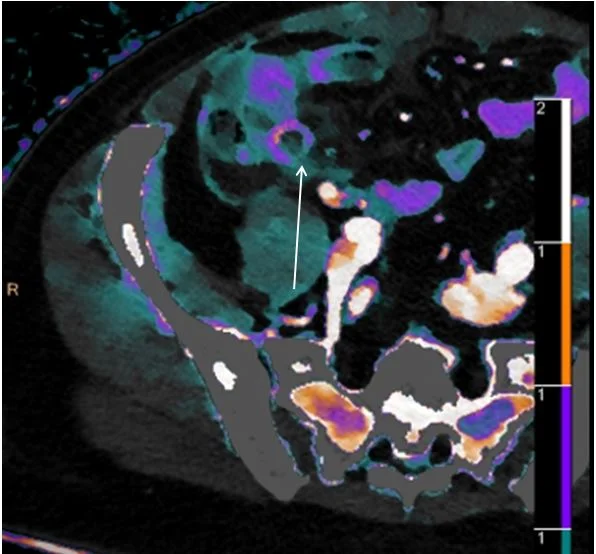

Iodine density overlay. Note focal discontinuity in appendix enhancement (white arrow).